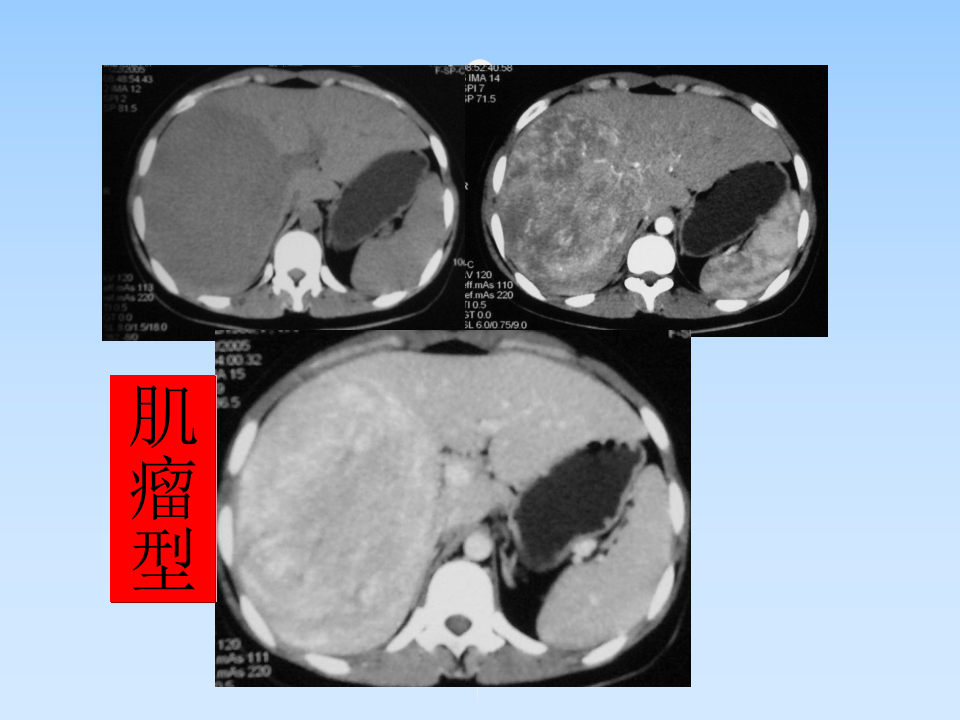

肝AML授课--曾蒙苏.ppt